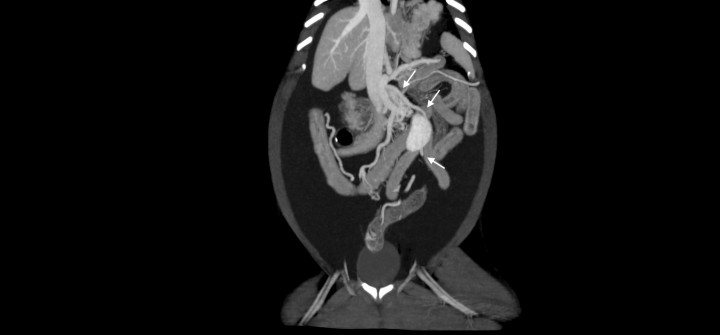

- Desde la vena esplénica, un vaso anómalo y aberrante, caudal y medial al riñón izquierdo, con la confluencia de otros vasos de menor calibre, era consistente con una comunicación esplenorrenal (Fig. 9A). También se observó la presencia de un vaso anómalo y tortuoso que partía de la vena pancreatoduodenal con dirección hacia caudal para terminar en la vena mesentérica caudal (Fig. 9B).

<p>Imágenes de tomografía computarizada dorsales tras la administración de contraste intravenoso, ventana de tejido blando y con proyección de máxima intensidad (MIP) con sumatorio de cortes. (<strong>A</strong>) Se observa un vaso anómalo a partir de la vena esplénica que se dirige hacia caudal y medial del riñón izquierdo (flechas). (<strong>B</strong>) Se aprecia un vaso anómalo a partir de la vena pancreaticoduodenal (flechas blancas) que desemboca en la vena mesentérica caudal (flecha negra).</p>

Imágenes de tomografía computarizada dorsales tras la administración de contraste intravenoso, ventana de tejido blando y con proyección de máxima intensidad (MIP) con sumatorio de cortes. (A) Se observa un vaso anómalo a partir de la vena esplénica que se dirige hacia caudal y medial del riñón izquierdo (flechas). (B) Se aprecia un vaso anómalo a partir de la vena pancreaticoduodenal (flechas blancas) que desemboca en la vena mesentérica caudal (flecha negra).